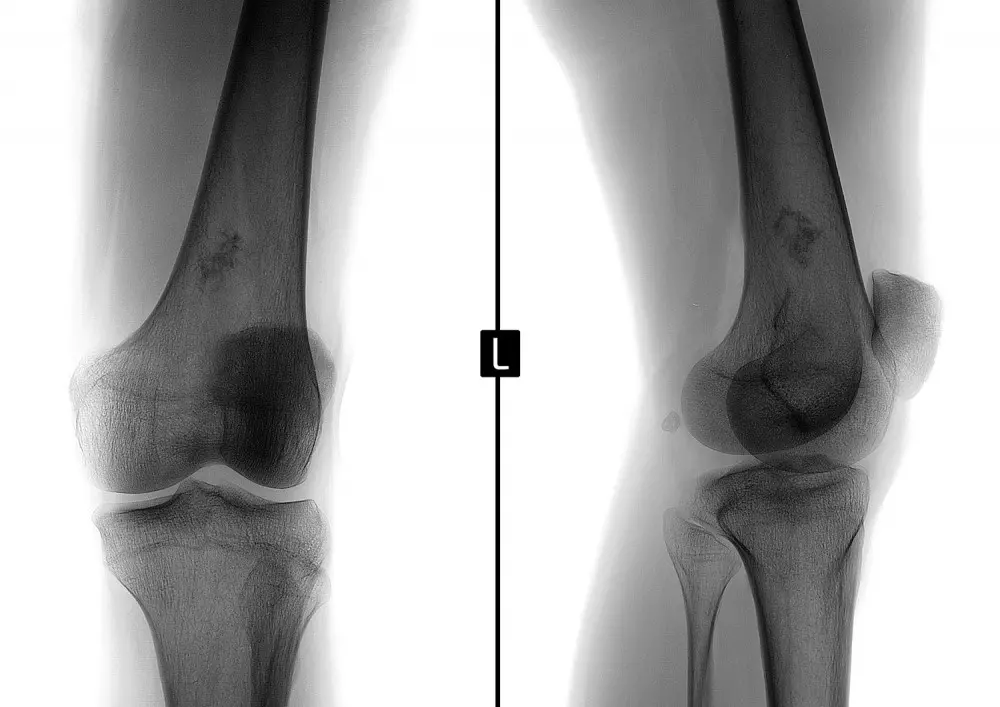

W dziale „Z praktyki gabinetu” znajdą Państwo tekst pt. „Kolano skoczka – metody lecznicze z punktu widzenia fizjoterapeuty”. Autor wskazuje na fakt, że zwiększona aktywność fizyczna, którą można zauważyć w ostatnich latach, sprzyja kontuzjom, przy czym szczególnie podatny jest na nie staw kolanowy o skomplikowanej budowie anatomicznej. Wśród tych kontuzji można wymienić właśnie kolano skoczka. „To uszkodzenie więzadła rzepki w miejscu, gdzie łączy się ono z rzepką. W tym newralgicznym miejscu sumują się różnego rodzaju mikrourazy, które w perspektywie czasu powodują degenerację tkanek” − pisze dr n. med. Kamil Klupiński.